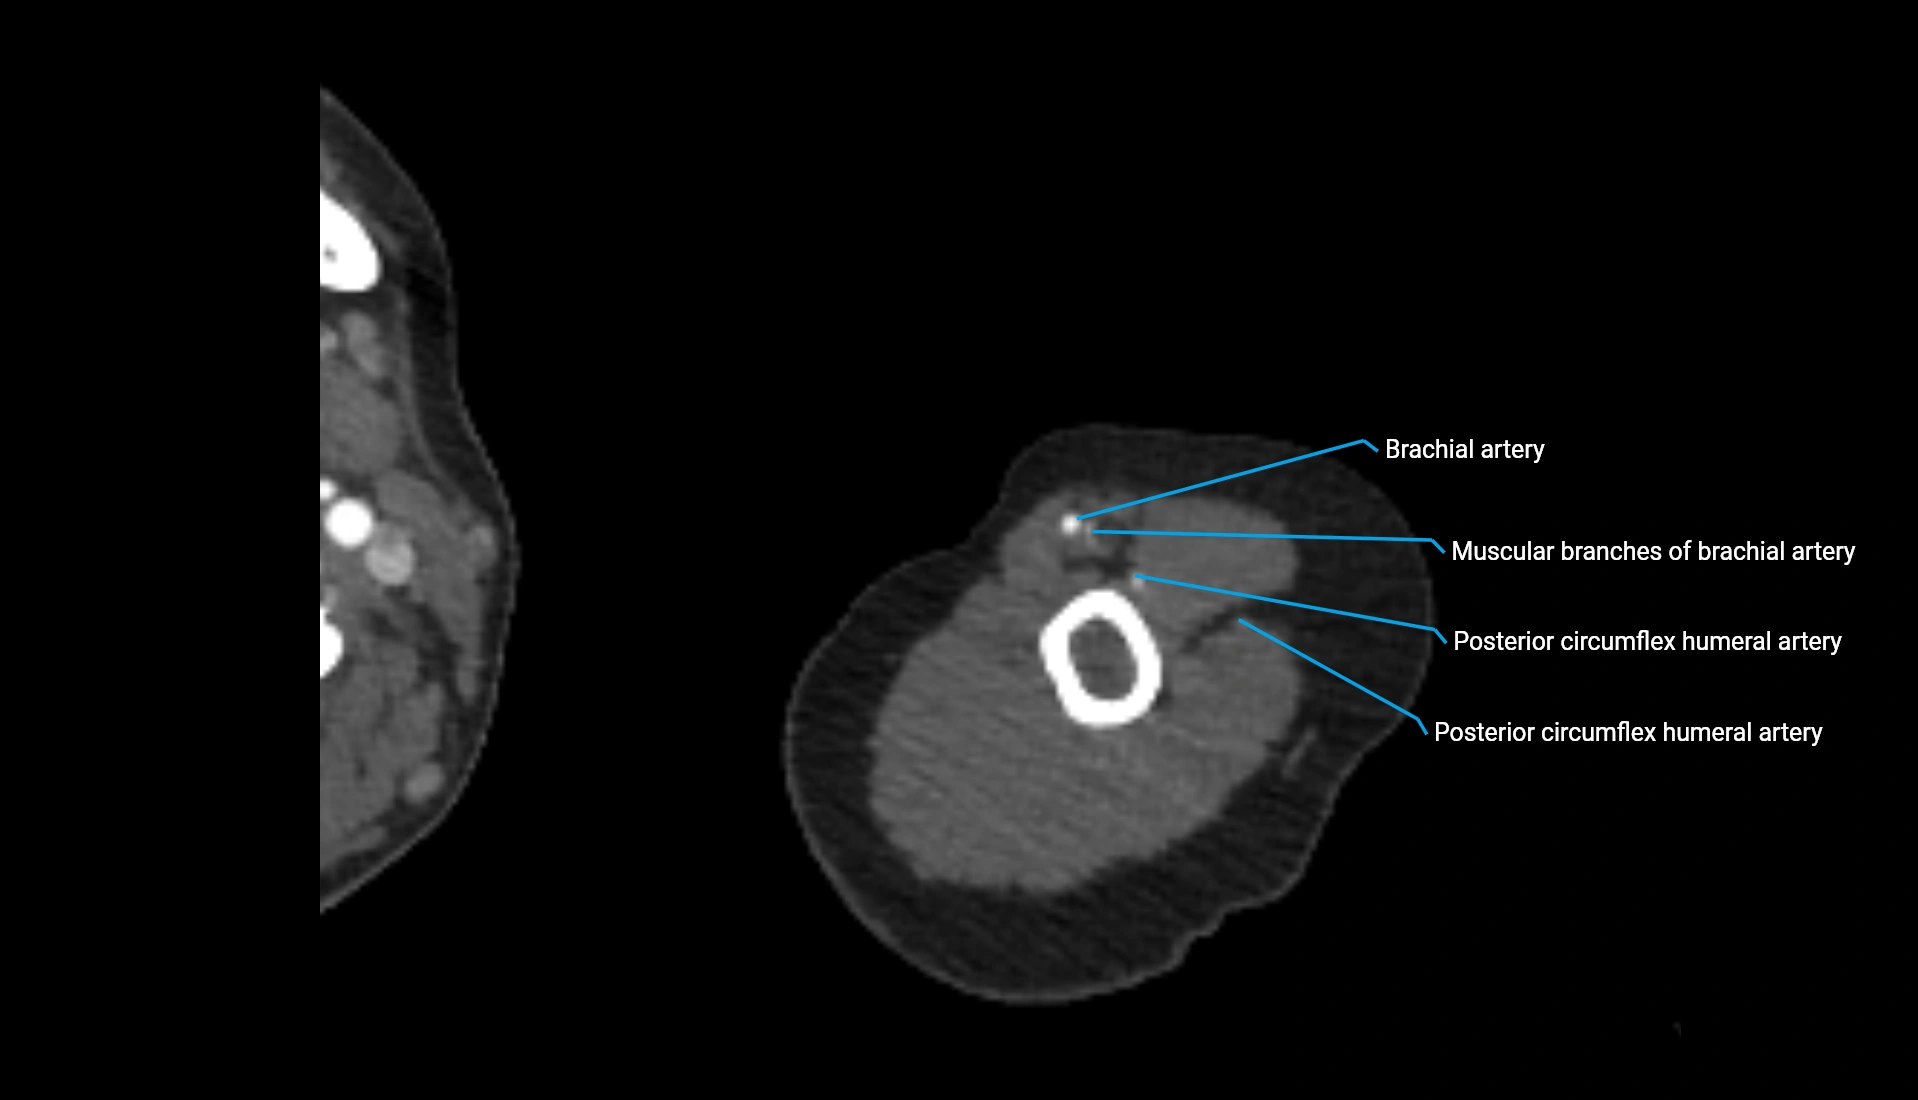

CT Appearance

Non-Contrast CT:

• Cortex: High-density, sharply defined

• Subchondral bone: Dense cancellous matrix

• Articular surface: Smooth concave contour articulating with the capitellum

• Excellent for evaluating bone integrity, alignment, and subtle fractures

Post-Contrast CT:

• Bone: No enhancement

• Joint capsule and synovium: Mild enhancement outlining the joint

• Improves contrast between soft tissues and bony margins

• Useful in detecting subtle joint abnormalities or postoperative changes